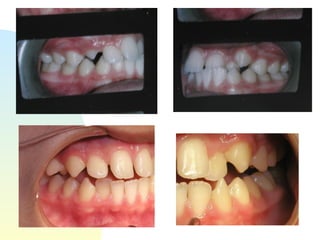

Patient   : J.R, male DOB :7/20/91, start of tx age: 12yr 9mo Ethnicity : American-born Hispanic, English-speaking Health Hx :  WNL, unremarkable Dental Hx :TMJ=WNL, OH=B+, midline=on, molar R&L= Cl 1, OB=40%, OJ= 1mm, dental anterior cross-bite, crowded max & mand anteriors, caries #15-O, #18-O,B, perio=WNL Psychosocial : Parents are separated,  1 younger sister,1 older sister.  Mom had ortho tx --- 4 premolars & 4-3rd molars extracted, “My braces hurt and I don’t want a lot of teeth pulled on my son”. Chief complaint :  “I don’t like the way my teeth stick out in front.”

Oct. 8, 2004 Uh-oh… Placed occlusal stops of Ketac-cem on #19& #30.  Lingual com- posite placed on #10 as bite ramp for #22.  Pt encouraged to chew sugarless gum. Reduced occlusal stops twice, 2 weeks apart.

Nov. 24, 2004 GAC, alpern style, Broadbent formula, .018 slot, .0175 twist  wire

Nov 30,2004 Both arches with 3strand twist wire

Feb 18,2005 NiTi Thermal Bioforce W/IonGuard  .016X.022 wires in place since Dec 15, 2004 (pt’s house burned down in Jan. 2005)

March 30,2005 Slight ARS between lower anteriors segmentally chain mand 4-4’s, 5&6’s

Oct. 8, 2004Uh-oh… Placed occlusal stops of Ketac-cem on #19& #30. Lingual com- posite placed on #10 as bite ramp for #22. Pt encouraged to chew sugarless gum. Reduced occlusal stops twice, 2 weeks apart.

Nov. 24, 2004GAC, alpern style, Broadbent formula, .018 slot, .0175 twist wire

Nov 30,2004 Botharches with 3strand twist wire

Feb 18,2005 NiTiThermal Bioforce W/IonGuard .016X.022 wires in place since Dec 15, 2004 (pt’s house burned down in Jan. 2005)

March 30,2005 SlightARS between lower anteriors segmentally chain mand 4-4’s, 5&6’s